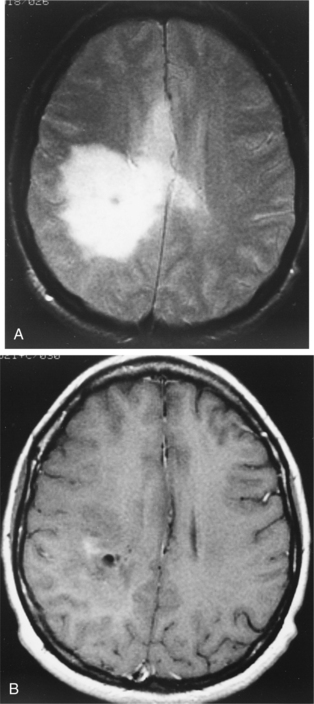

About 20% to 50% of adults with brain tumors develop seizure activity. The cerebral edema causes hyperactive cells, which produce abnormal, paroxysmal discharges or seizure activity.106 Seizures may be the first presenting sign of a tumor. In patients presenting with seizures, detection of low-grade gliomas is becoming increasingly frequent with magnetic resonance imaging (MRI). See Fig. 30-3 for an MRI scan of a low-grade glioma presenting with a seizure. In the later stages of illness, seizure activity is present in 70% of patients.93 A common feature of a tumor-related seizure is its repetitive nature, with seizures being very stereotypical in a given patient.137

Figure 30-3 Magnetic resonance imaging (MRI) of a low-grade glioma. A, T2-weighted image. B, T1-weighted image, gadolinium contrast with minimum enhancement. The images are typical of this tumor, which is being detected with increasing frequency by MRI in seizure patients. Many are invisible on computed tomographic scans. (From Goldman LM, Ausiello D, eds: Cecil textbook of medicine, ed 22, Philadelphia, 2004, Saunders.)